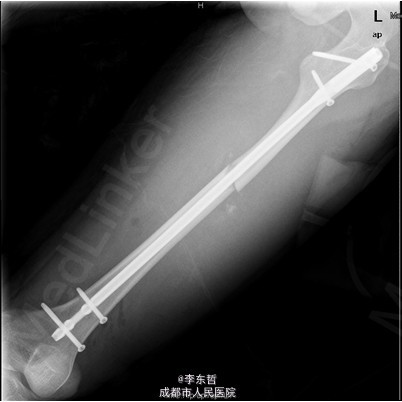

患者男,19岁,因“车祸伤致左下肢活动障碍5小时”入院。5小时前,患者骑电瓶车不慎与另一电动摩托车相撞倒地,当即感左大腿疼痛,畸形,活动受限,右小腿皮肤挫伤、出血,无头晕头痛,无大小便失禁。就诊于当地医院,检查提示:左股骨中段横行骨折。急诊行左大腿夹板外固定,右小腿清创缝合术,术后未进一步治疗,患者为进一步诊治来我院,急诊以左股骨中段骨折收入我科。 自患病以来,患者一般情况尚可,精神睡眠可,小便正常,大便未解。

查体:左大腿夹板固定,肿胀明显,短缩、畸形,右小腿内前方可见一长约5cm创口,已缝合,内植引流条一根,无明显肿胀。左大腿中段环周压痛,可扪及骨折断端,右小腿无明显压痛,双下肢感觉正常。左膝及髋关节明显活动受限,左足背及右下肢活动正常。 辅查:外院X片示:左侧股骨中上段可见骨质断裂征象,断端分离、错位、重叠,周围软组织肿胀;双侧胫腓骨、左膝关节各骨及左踝关节未见确切骨质断裂征象。

初步诊断:1、左股骨中段横行骨折,2、右小腿皮肤软组织裂伤清创缝合术后。 诊疗计划:1、向患者及家属交待病情及注意事项。2、向上级医生汇报患者病情。3、完善术前相关检查。4、给予皮肤牵引、抬高患肢等对症处理。5、拟进一步手术治疗。6、密切观察病情变化,根据病情及时处理